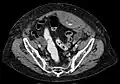

Rectus sheath hematoma seen on axial CT – with active bleeding under Marcoumar -